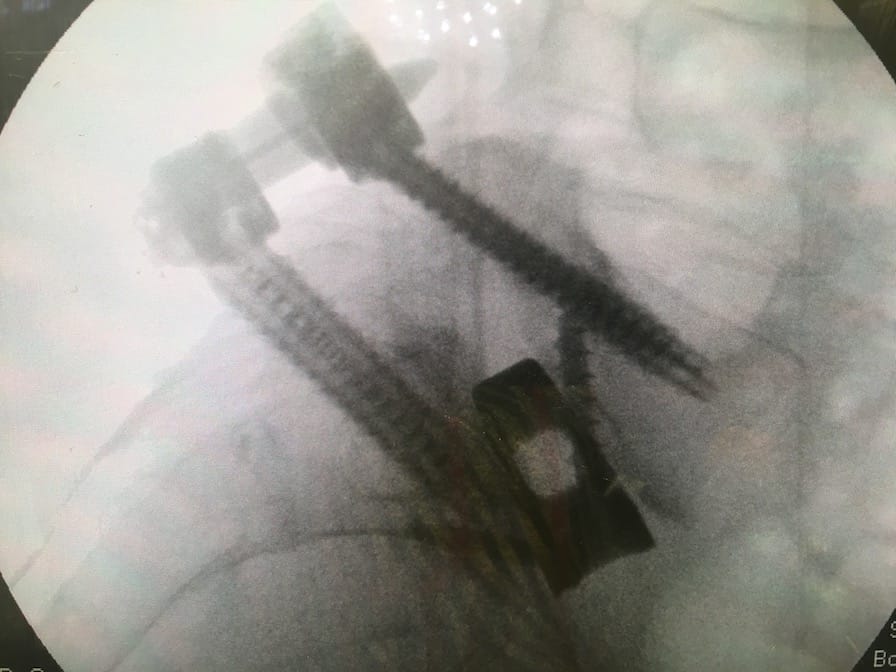

My back surgery in 2018 has been really successful, from being told I may not compete again to actually getting back to racing has been a better result than I hoped for. Also the day-to-day pain I used to have has disappeared. The only problem I have is the screws in my back protrude a bit. I don’t notice them too much but there is constant irritation at the site of screw, it’s low lying pain and I just tend to get on with things and ignore it, but recently it has got a little worse.

This may be an effect of lockdown and maybe not having as much physio treatment? Not really sure. I had a consultation with the surgeon and after looking at my back he decided they need to come out. I am booked in for September to get them out, after which, I should be able to take further strides forward. So, no racing in September but hopefully before the year is out, I will race in anger…again!

So, with the current uncertainty still continuing, we spoke to Helen’s back surgeon regarding the screws and plates she has in her spine. They were there to make sure the fusion achieved in her major surgeries held and bone was allowed to grow. Two years on from the surgery and the Doctor took one look at them and said they need to come out. One of them sticks out of her back so far, I worry about Helen crashing in a race as she has been known to before. If she lands on that screw, it’s coming out of the skin. In addition to this, Helen and I were swimming a few weeks ago where she dived in shallow water, landed on a rock and has cracked ribs so breathing wasn’t much fun and training was low level.